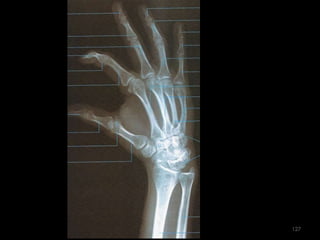

Incidência PA Mão118

119

120

Incidência em extensão e flexão – látero-medial da mão121

Incidência oblíqua PA da mão125

126

127

Incidência AP do polegar128